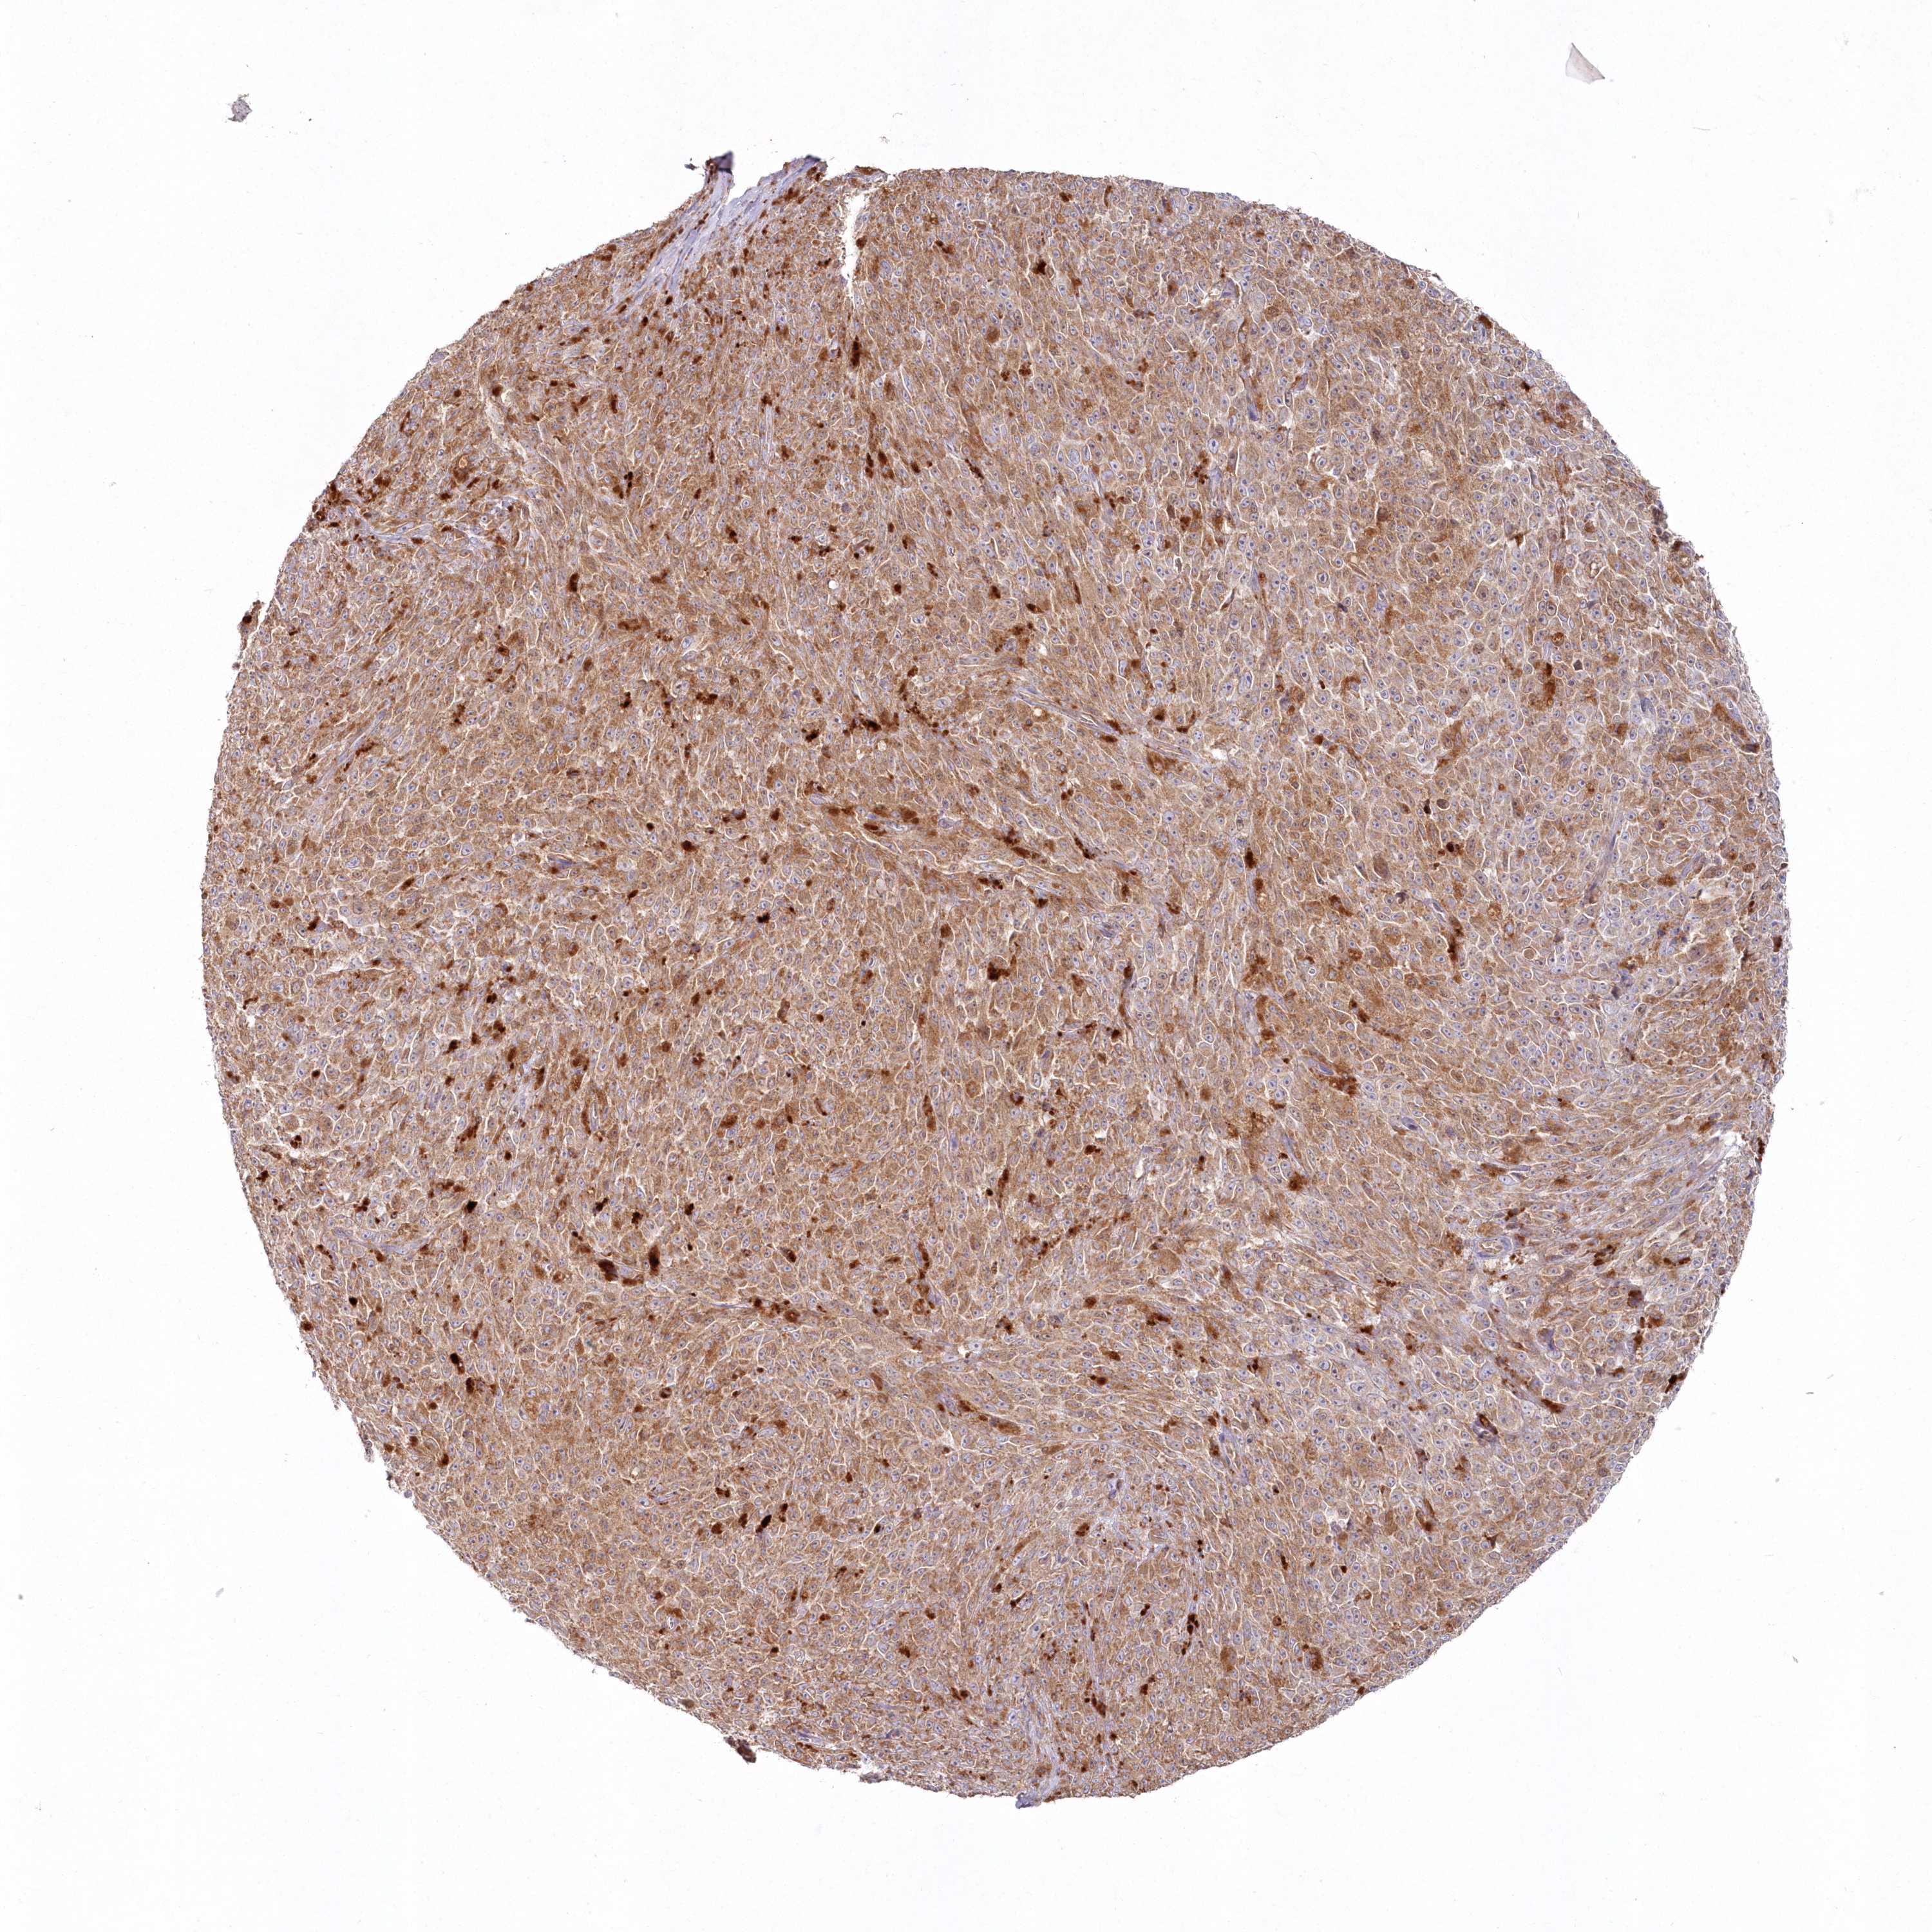

MELANOMA - Protein expressioni

A mouse-over function shows sample information and annotation data. Click on an image to view it in a full screen mode. Samples can be filtered based on level of antibody staining by selecting one or several of the following categories: high, medium, low and not detected. The assay and annotation is described here.

Note that samples used for immunohistochemistry by the Human Protein Atlas do not correspond to samples in the TCGA dataset.

Antibody stainingi

Antibody staining in the annotated cell types in the current human tissue is reported as not detected, low, medium, or high, based on conventional immunohistochemistry profiling in selected tissues. This score is based on the combination of the staining intensity and fraction of stained cells.

Each image is clickable and will lead to virtual microscopy that enables deeper exploration of all samples and also displays staining intensity scores, fraction scores and subcellular localization as well as patient and tissue information for each sample.

Antibody HPA037770

Antibody HPA037771

Staining

High

Medium

Low

Not detected

Intensity

Strong

Moderate

Weak

Negative

Quantity

>75%

75%-25%

<25%

None

Location

Nuclear

Cytoplasmic/membranous

Cytoplasmic/membranous,nuclear

Malignant melanoma, NOS

Malignant melanoma, Metastatic site